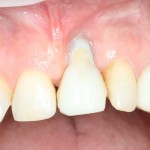

Можно передавать пациента ортопеду для временного протезирования. Что он и делает:

Важным условием гарантийных обязательств в нашей клинике являются профилактические осмотры, которые проводятся один или два раза в год (см. Гарантии и Долгосрочное наблюдение). Через полтора года после протезирования, при очередном осмотре мы сделали фотографии и снимок: